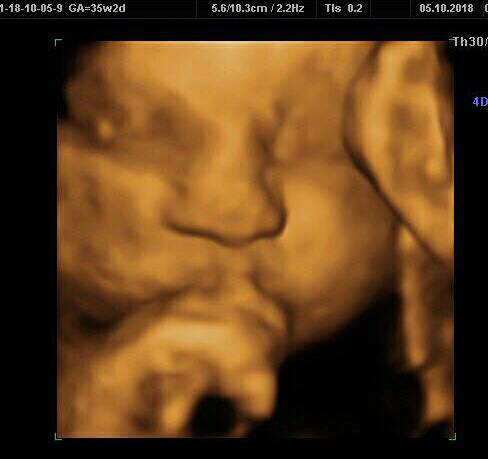

Wizyty u ginekologa - usg